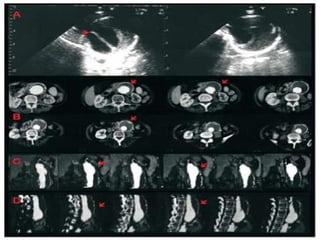

DiagnósticosDiagnósticos